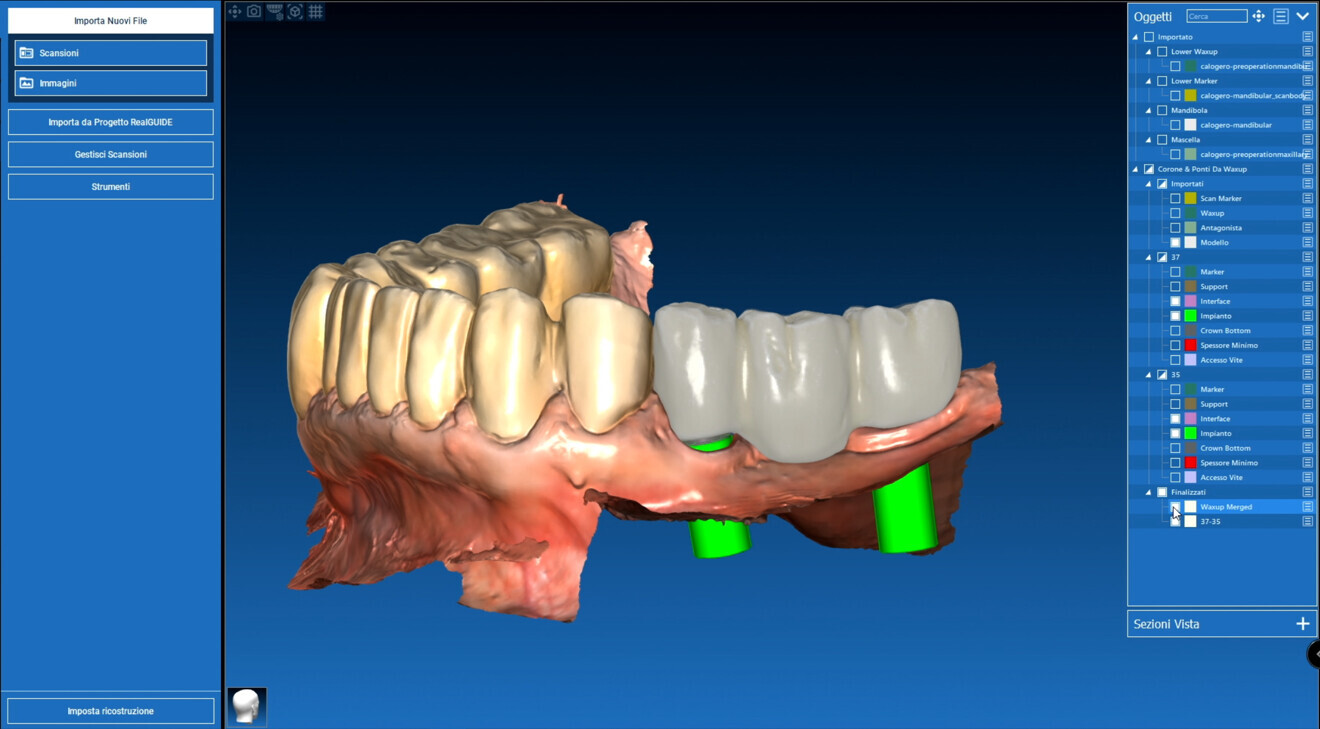

Design Once the STL file of the scan had been obtained, the prosthesis was digitally designed in the RealGUIDE CAD+ software (3DIEMME), according to the following criteria:

precise fit on the ProCam Ti-bases;

passivity of the structure to reduce stress;

occlusion optimisation; and

natural aesthetics through advanced design.

The implant base was then fabricated using Ti-base custom interfaces. A key technical detail comes into play here: the ability to take advantage of a special 50 μm printing offset, designed to ensure the appropriate space for the cement and optimise the accuracy of fit between the 3D-printed part and the Ti-base. This seemingly minor detail turned out to be essential for achieving effective cementation, eliminating any tension and ensuring perfect adhesion of the anatomical part to the implant base. The ability to modify the design in real time made the design phase extremely efficient (Figs. 4a-c). The use of CAD/CAM technologies in fixed implant prosthetics has shown excellent results in terms of precision and fit.3

Figs. 14a–c:: Bridge design in RealGUIDE CAD+.